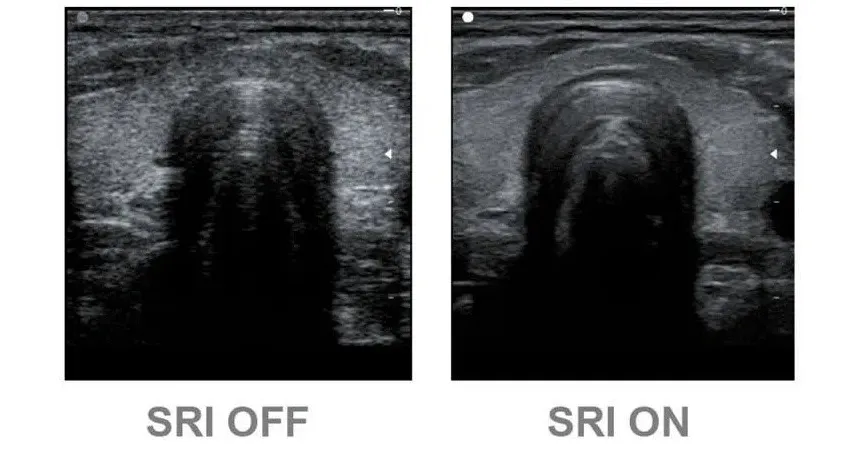

Speckle Reduction Imaging (SRI)

Технология значительно снижает количество нежелательных пятен и зернистости. В результате фильтрации улучшается связь между неоднородными участками тканей различных органов, значительно увеличивается пространственное и контрастное разрешение. Эхограмма становится более легкой для «чтения» за счет повышения качества визуализации контуров, структур тканей и мелких деталей.